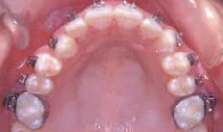

Bên cạnh đó, có thể quan sát răng cửa xoay, răng nanh, răng hàm nhỏ và răng hàm lớn từ phía mặt nhai hay cạnh cắn qua gương giúp đặt mắc cài chính xác hơn theo trục răng.

Hình 11a Một ví dụ lâm sàng của gắn mắc cài xoay. Điều chỉnh hoàn toàn sự xoay có thể đạt được trong giai đoạn sớm của điều trị mà không cần thêm phương pháp đặt biệt nào khác. Xem thêm Hình 11b.

Hình 11b